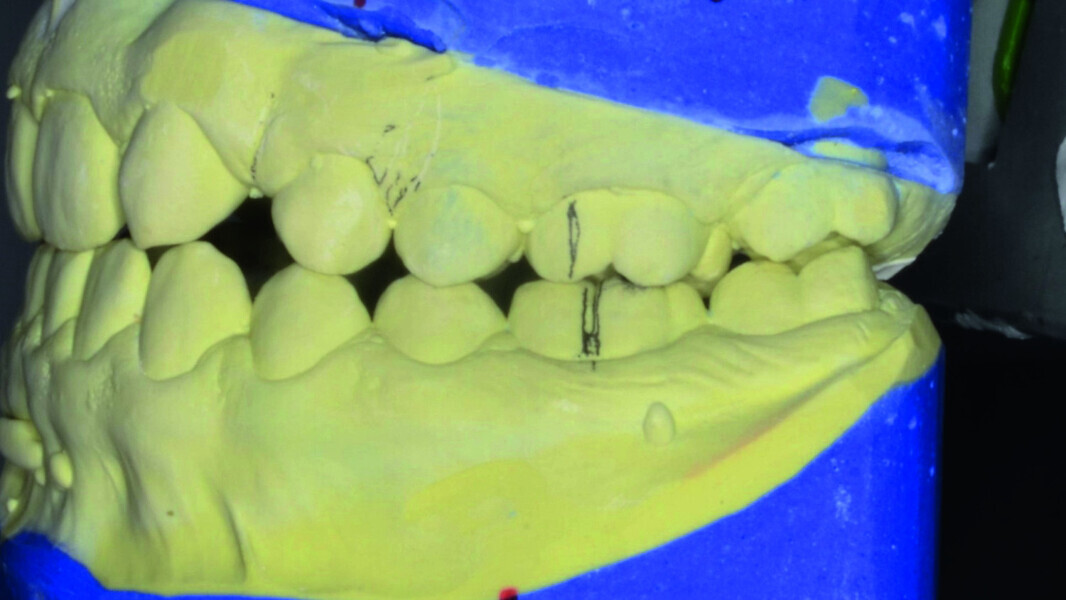

Orthodontic management of maxillary lateral incisors agenesis